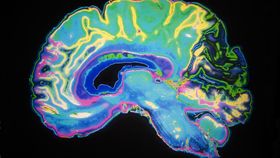

Alzheimer's disease is caused by the abnormal buildup of proteins – amyloid-β and tau – in the brain. This can eventually lead to a form of dementia characterized by progressive loss of cognition involving memory, difficulty with problem-solving, confusion, and disorientation. However, it’s known that changes in the brain involving these proteins can start to occur decades before clear symptoms emerge.